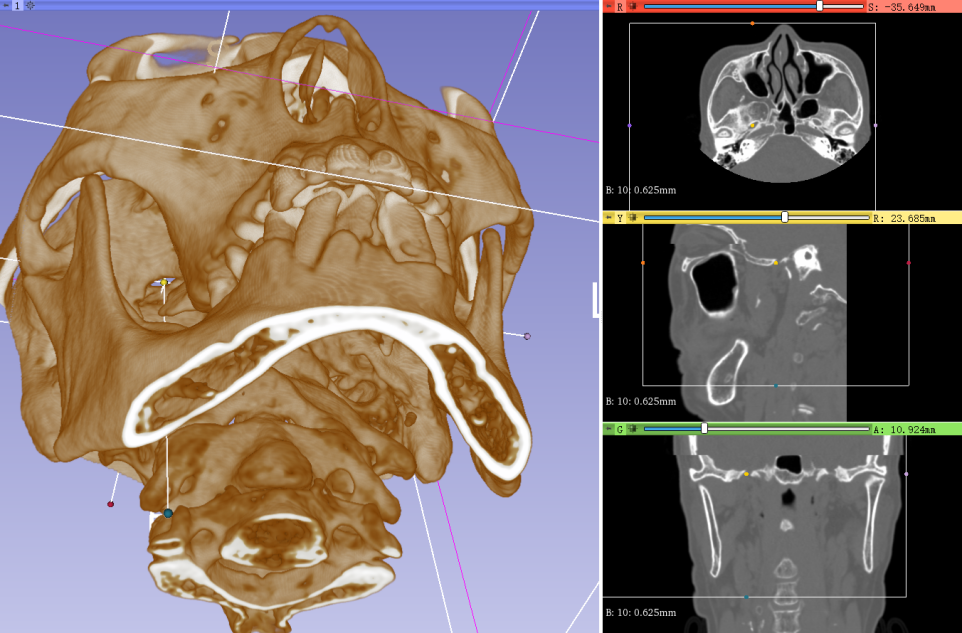

图1利用3Dslicer软件对DSA数据进行三维重建,精准评估卵圆孔及Meckel’s囊解剖结构

手术充分发挥复合手术室DSA设备的平台优势,将精准医疗理念贯穿全程。术前,依托DSA的高清三维重建技术,手术团队可从任意角度立体呈现颅底卵圆孔的细微解剖结构,精确测量其大小、形态与走向,并对穿刺路径反复模拟推演,确保每个角度安全无误。术中,依托双平面DSA的动态成像功能,采用“正位定向、侧位定深”的双轨验证策略——正位透视实时校准穿刺针与卵圆孔的对准方向,侧位影像精准把控进针深度,使穿刺针一次性精准抵达三叉神经半月结目标靶点。整个手术从麻醉到结束仅用时30分钟,患者术后即刻清醒,疼痛完全消失,肢体活动正常,真正实现了“针入痛止”的立竿见影之效。